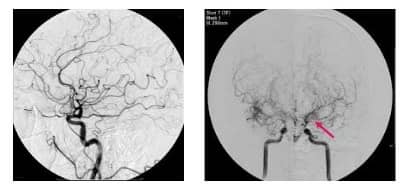

모야모야병은 뇌혈관조영술로 진단되며, 자세한 뇌혈류 검사 결과에 따라 치료가 진행됩니다.

모야모야병은 뇌의 주요 혈관들이 점차 좁아지는 질병입니다. 이로 인해, 뇌에 필요한 혈액 공급이 제대로 이루어지지 않게 됩니다. 이런 현상을 보완하기 위해 뇌 내의 작은 혈관들이 활성화되어 더 많이 형성됩니다.

이 작은 혈관들의 형태가 연기처럼 흐르는 모양을 닮아 '모야모야'라는 이름이 붙여진 것입니다. 이 이름은 일본어에서 유래하였으며 연기가 구름처럼 피어오르는 모양을 뜻하는 말에서 비롯되었습니다.